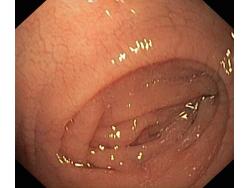

Celiakia